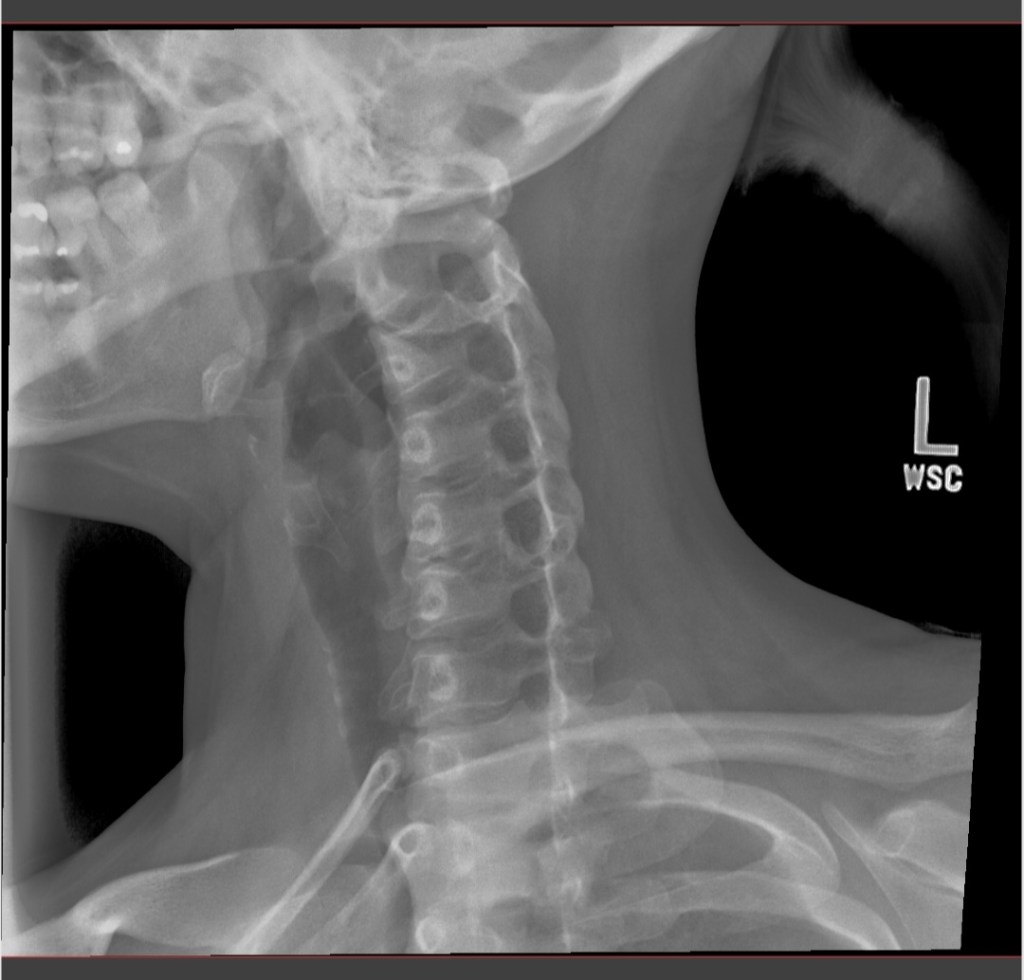

I was given a prescription for meds and had x-rays taken of my neck and spine – I felt silly when I had to get some of the x-rays with my mouth open wide.

My X-rays showed degenerative disc disease in my C-4 to C-5 and C-5 to C-6 spine area, with bone spurs and muscle spasms. No wonder my neck has been killing me lately.